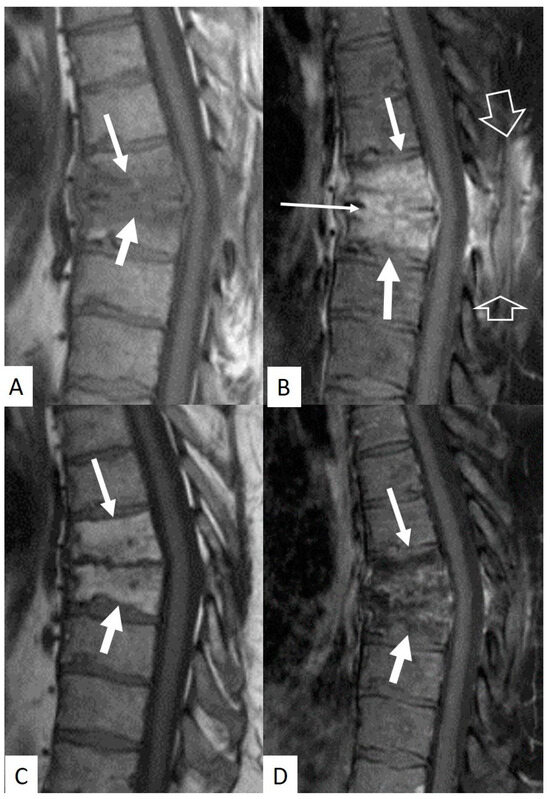

3.4. Imaging